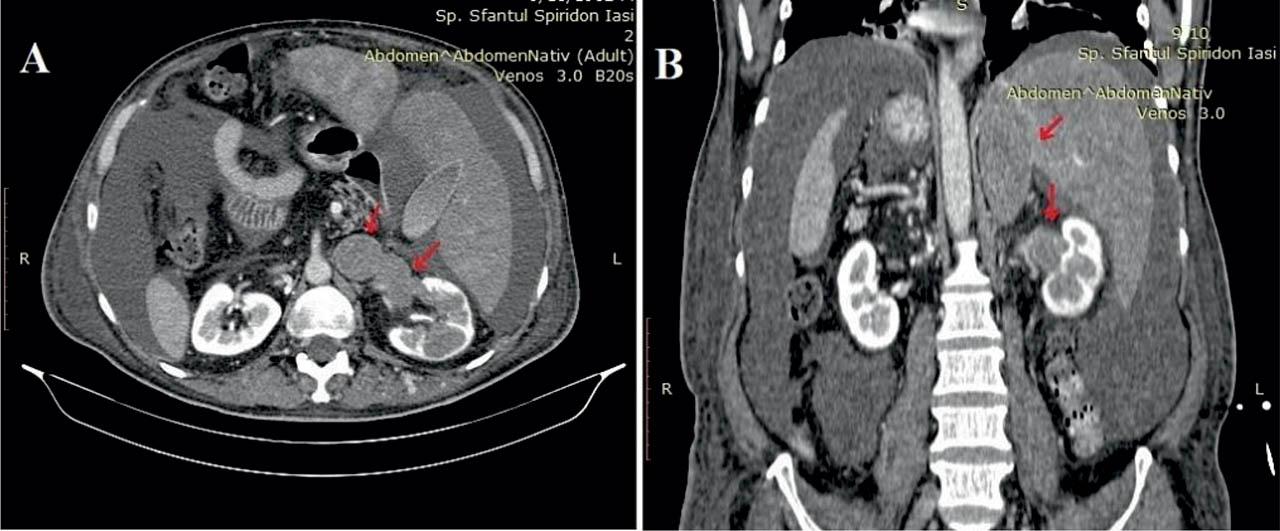

Figure 4

A. Abdominal CT venous phase - axial view. The mass descends in the renal segment, on both renal veins, infiltrating the left kidney with diminished peripheral renal parenchyma preserved. B. Abdominal and pelvic CT venous phase - coronal view. Tumor indicated by the red arrows. Appearance of an infiltrated subcutaneous adipose tissue at the abdominal wall and both thighs.